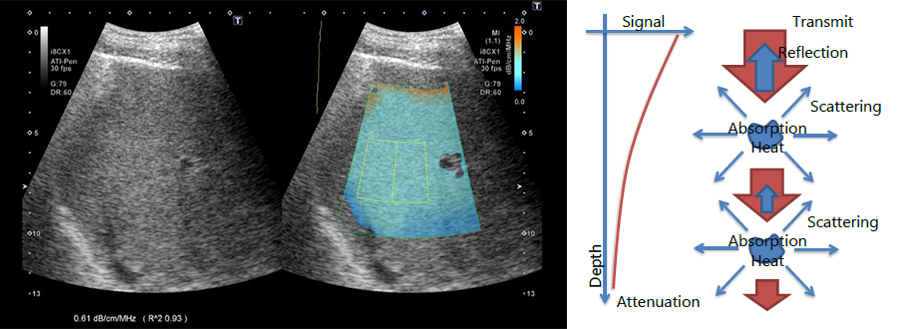

Стеатометрія печінки - це новий інструмент, для кількісної оцінки стану печінки, і найбільш безпечна альтернатива біопсії. Суть її полягає у вимірюванні коефіцієнта загасання (КЗ в дБ/см).

Стеатометрія стала інноваційним методом дослідження, дозволила виміряти жировий шар, за допомогою УЗ-апарату Canon Medical, і зробила виявлення, діагностування та лікування стеатозу на ранніх стадіях, незрівнянно комфортною процедурою, як для пацієнта, так і для лікаря.